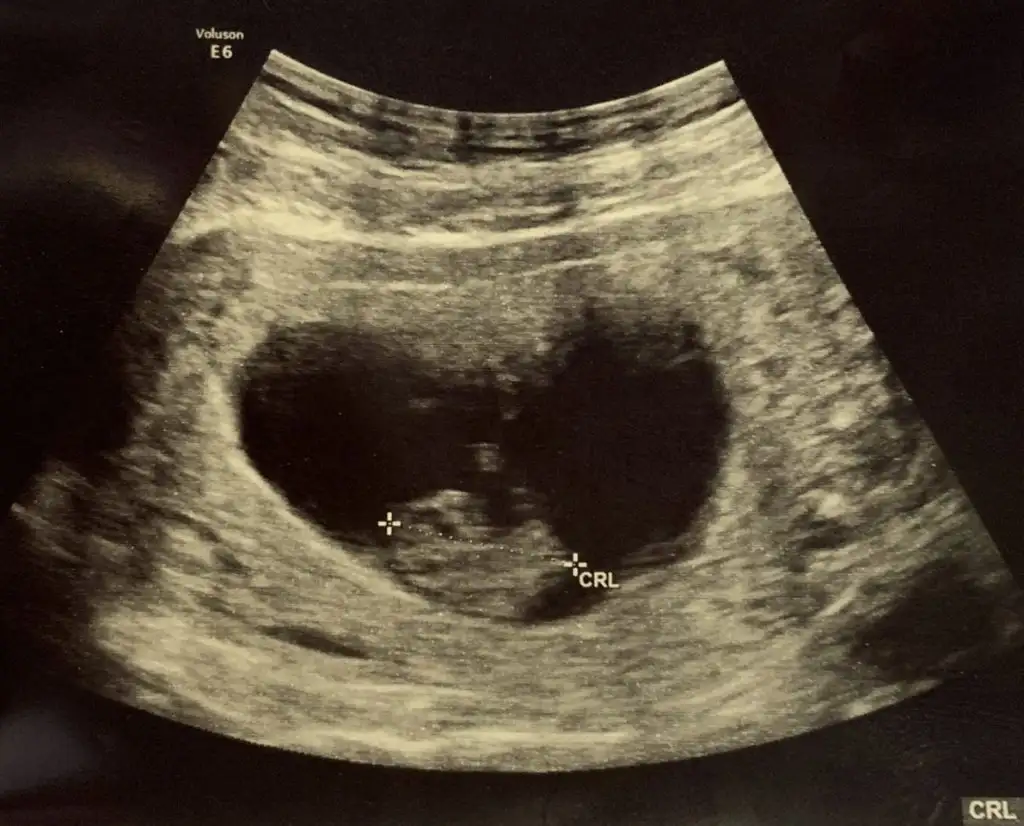

sandriyon tahminlerinizi alayım tatlımlar karından çekildim bugün çok fotojenik değil miyiz ama

ne guzel buyumus bebısler goruyoruz :) kız annesı :)Papatyamaviss bugun 9+1 günlüğüz kontrolden geldik.teyzesi bizede bi cinsiyet tahmininde bulunurmusun